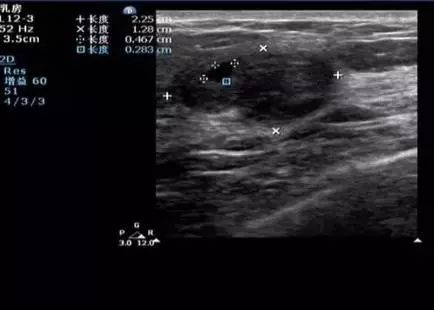

2.低回声、无回声、边界清楚、边界不清

低回声:“结节”黑一些

无回声:“结节”更黑一些

边界清楚和边界不清:描述肿块在图像上是否清晰可辨

解读:在乳腺超声报告里,通常会形容结节是“低回声”或“无回声”,这同样是一个描述性语言。在超声的黑白图像上,各种不同性质的“结节”自然有的黑一些(低回声),有的更黑一些(无回声),似乎也没有特别客观的界定标准。“边界清楚”或“边界不清”则是形容这些“结节”在图像上是否清晰可辨。不能说“边界不清”就是恶性的,或者“边界清楚”就是良性,这还需要医师具体分析。